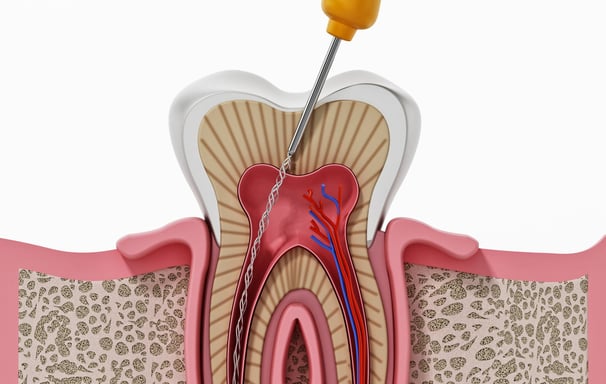

Es el procedimiento para limpiar, desinfectar y sellar los conductos internos del diente cuando la pulpa está infectada o inflamada. Es esencial para salvar el diente.

Tratamiento de Conducto

Se aplican medicamentos dentro de los conductos radiculares para controlar infecciones y promover la curación. Estos medicamentos ayudan a desinfectar el área antes del sellado final.

Colocación de medicamentos intraconducto